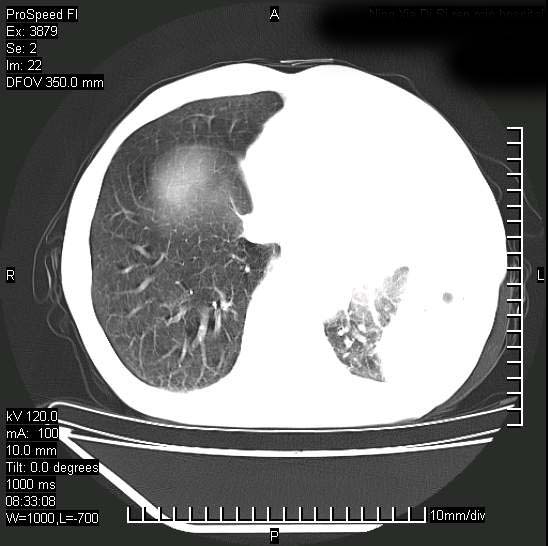

以下是引用37度在2008-6-6 11:20:00的发言:[br]1.包裹性积液,多考虑结核性;[br]2.穿刺术后改变。

以下是引用312nanyang在2008-6-6 15:12:00的发言:[br]基本支持楼主意见[br]疑问?左下肺支气管旁的软组织(16层)密度怎么解释?淋巴结还是斜裂胸膜增厚所致?能否增强进一步检查